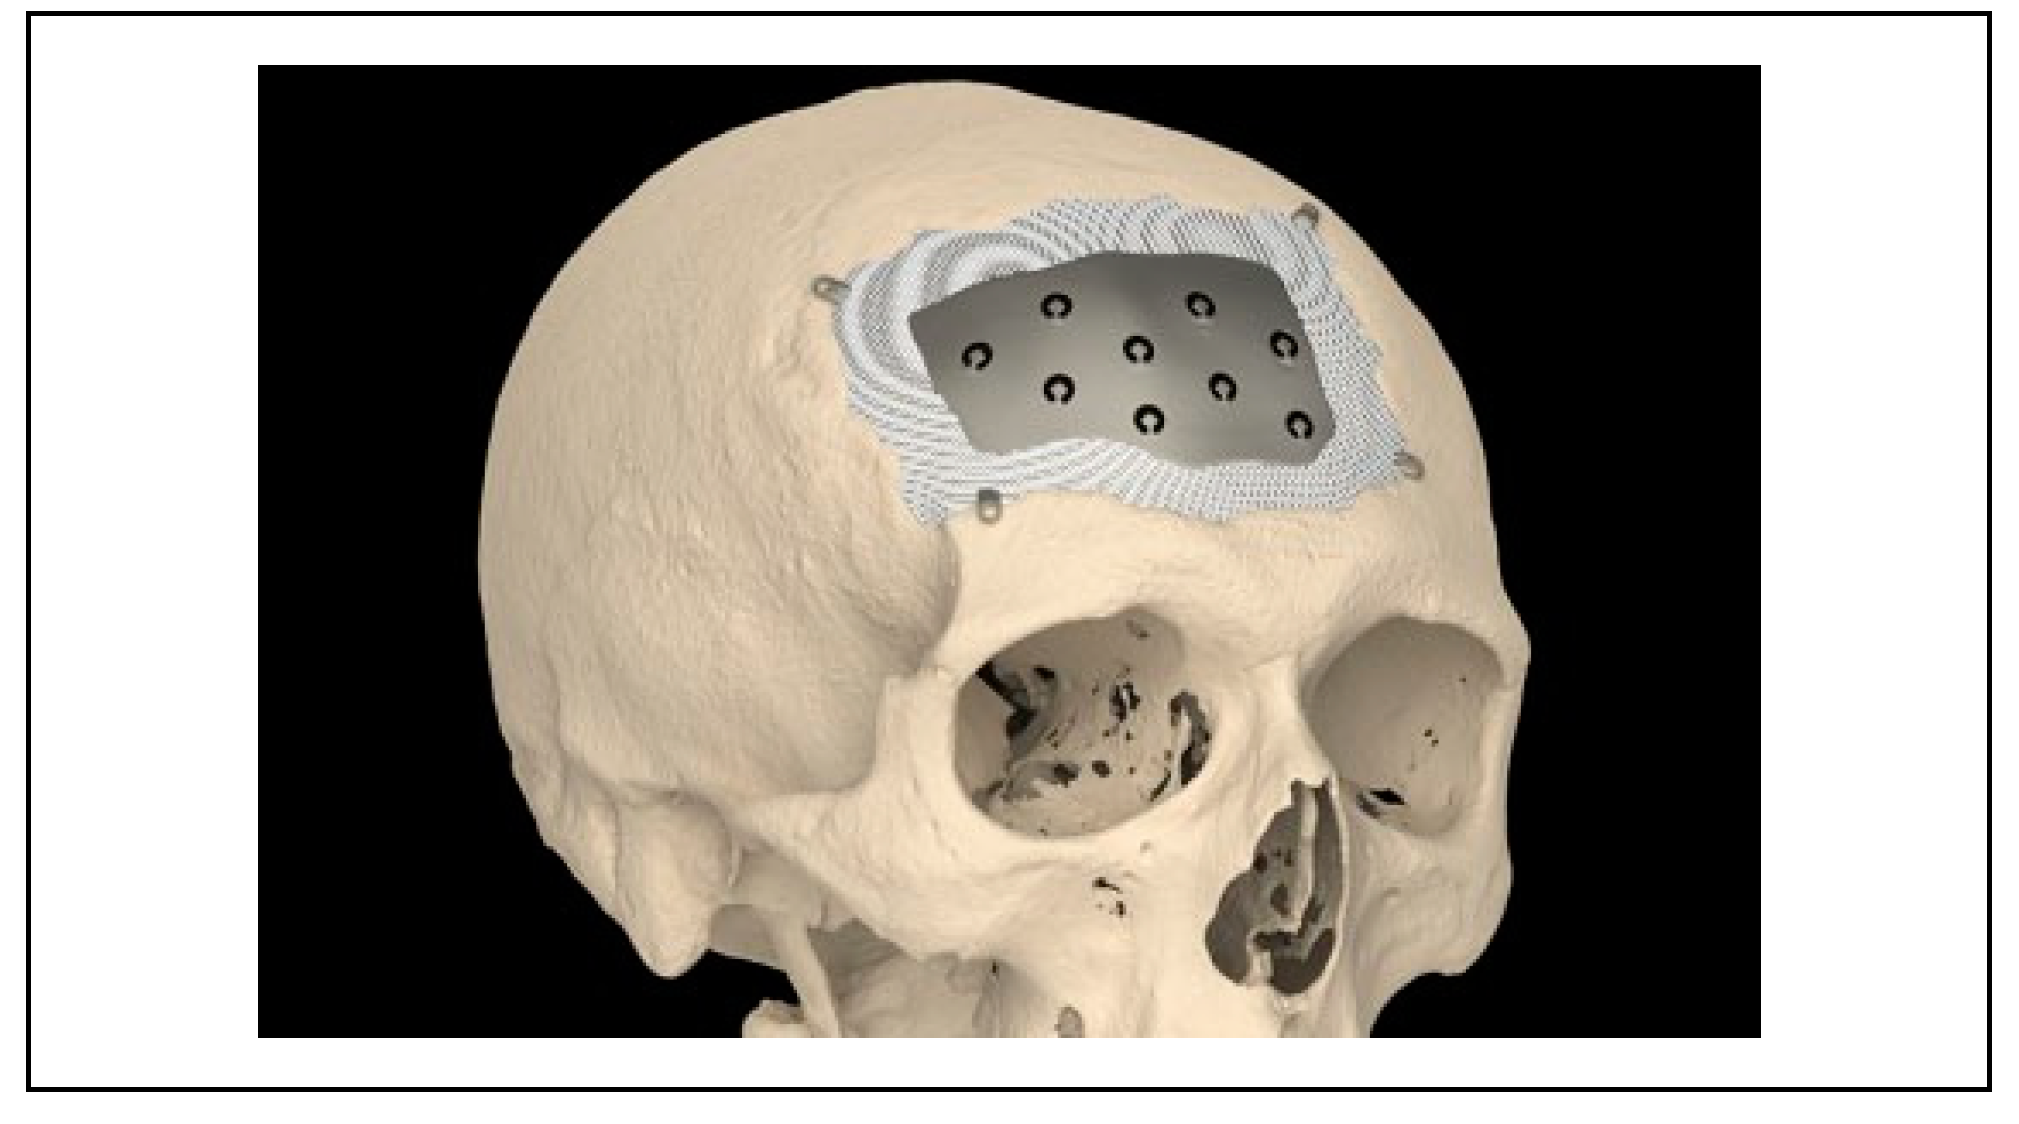

Ceramic 3D-Printed Titanium Cranioplasty

Technical Aspects